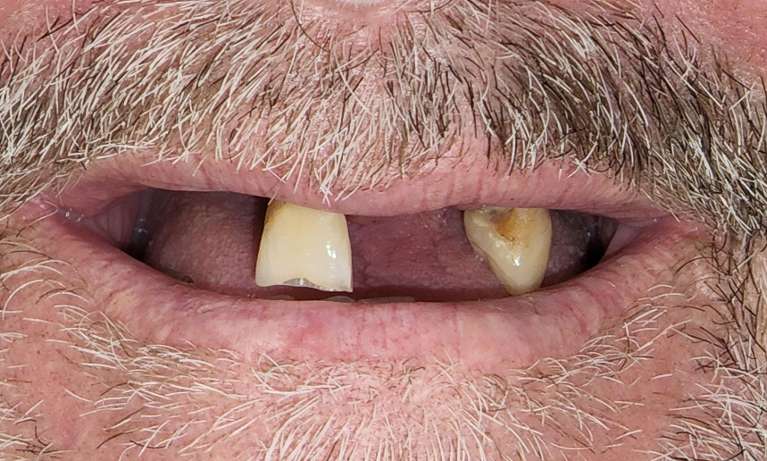

This patient's two missing teeth were expertly replaced with dental implants. The transformation not only restored their natural smile but also improved overall dental function.